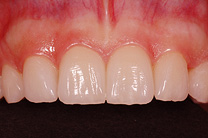

Ist ein Zahn sehr stark oder bis unter das Zahnfleisch zerstört, kann er nicht mehr mit einer herkömmlichen Kunststofffüllung versorgt werden. Der noch vorhandene Restzahn lässt sich nur noch durch eine Krone restaurieren. Sie besteht aus einem individuell gegossenen Metallgerüst, auf welches in mehreren Schichten Keramik aufgebrannt wird oder kann als rein vollkeramische Krone hergestellt werden, was zu einer noch höheren Ästhetik führt.

Die Restauration eines Zahnes mit einer Krone ist aufwendig. In einem ersten Schritt wird Karies und das alte Füllungsmaterial vollständig entfernt und der Zahnstumpf wieder aufgebaut. Eine präzise Abformung der Situation dient dem Zahntechniker als Grundlage für ein Gipsmodell, auf dem er die Krone herstellt. Sofern Farbe und Form perfekt stimmen, kann die Krone in einer zweiten oder dritten Sitzung beim Zahnarzt zementiert werden. Für die Zeit zwischen Präparation des Zahnes und dem definitiven Zementieren der Krone wird der Zahn mit einem individuell hergestellten Provisorium versorgt.